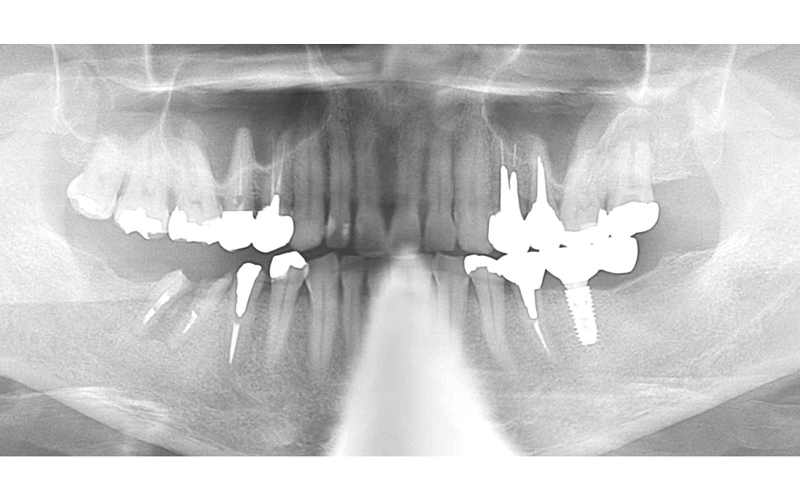

初診時パノラマ

| 備考 | 【治療詳細】 右下の6番延長ブリッジの根が太く長い土台の金属が入っており、歯根破折しておりました。 左側の7番も同様に歯根破折しておりました。 左側インプラント治療後。患者さん希望の為、インプラント体1本に対して2本分の被せ物で補綴。 案の定、内部のネジの緩みが何度か発生。 右下が保存不可能になった為、インプラント2本埋入。 右下のインプラントが経過良く、左下のインプラントの追加を希望されましたので、被せ物をいったん除去して追加埋入。 補綴完了後の口腔内。現在最初のインプラント埋入から5年経過しておりますが、経過良好です。 左下6番のみ被せ物の内部に金属を使用していますが、他はフルジルコニア。 アクセスする穴にレジンを使用しています。 |